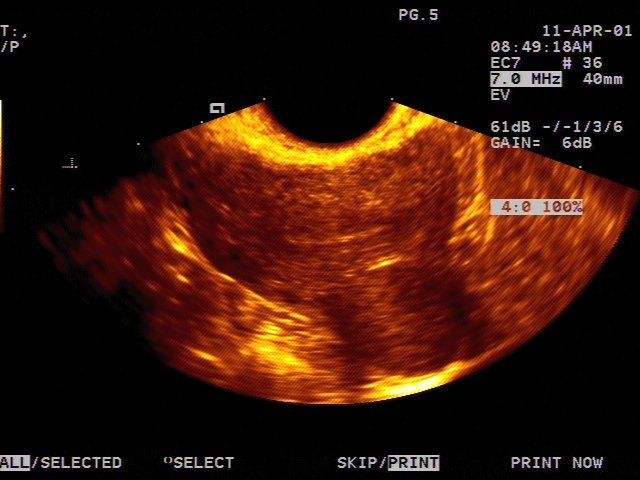

Icd 10 subserosal leiomyoma of uterus

- Icd 10 leiomyoma of uterus